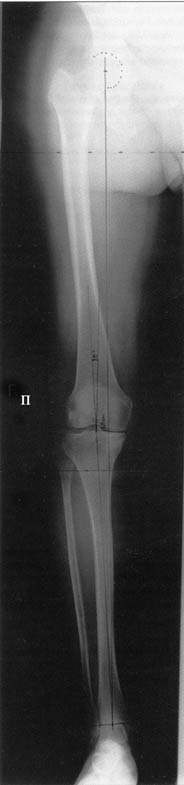

AC> Вот, с учетом и без учета, и на разных уровнях...

И зачем латерализация периферического фрагмента. Я всегда делаю медиализацию. См схему. И для данного случая медиализация подходит как нельзя лучше.

a> Я всегда делаю медиализацию. См схему. И для данного случая

Медиализация - это чисто эстетический прием, как я понимаю. Поскольку если делать остеотомию ниже вершины деформации, для восстановления оси надо делать смещение по ширине, в данном случае как раз латерализацию.

Красива...

Это значительно улучшает эстетический эффект, придавая полноту ногам.

И при этом не выходит за пределы нормальной оси.

Мне представляется оптимальным на уровне 3-4 линии (т.е. как раз посредине отмеченной зоны). Если рассчимтываешь делать медиализацию, то параллельно суставной поверхности, иначе просто не сдвинешь без джистракции - отломки зацепятся. Если без медиализации - то вообще не имеет значения.